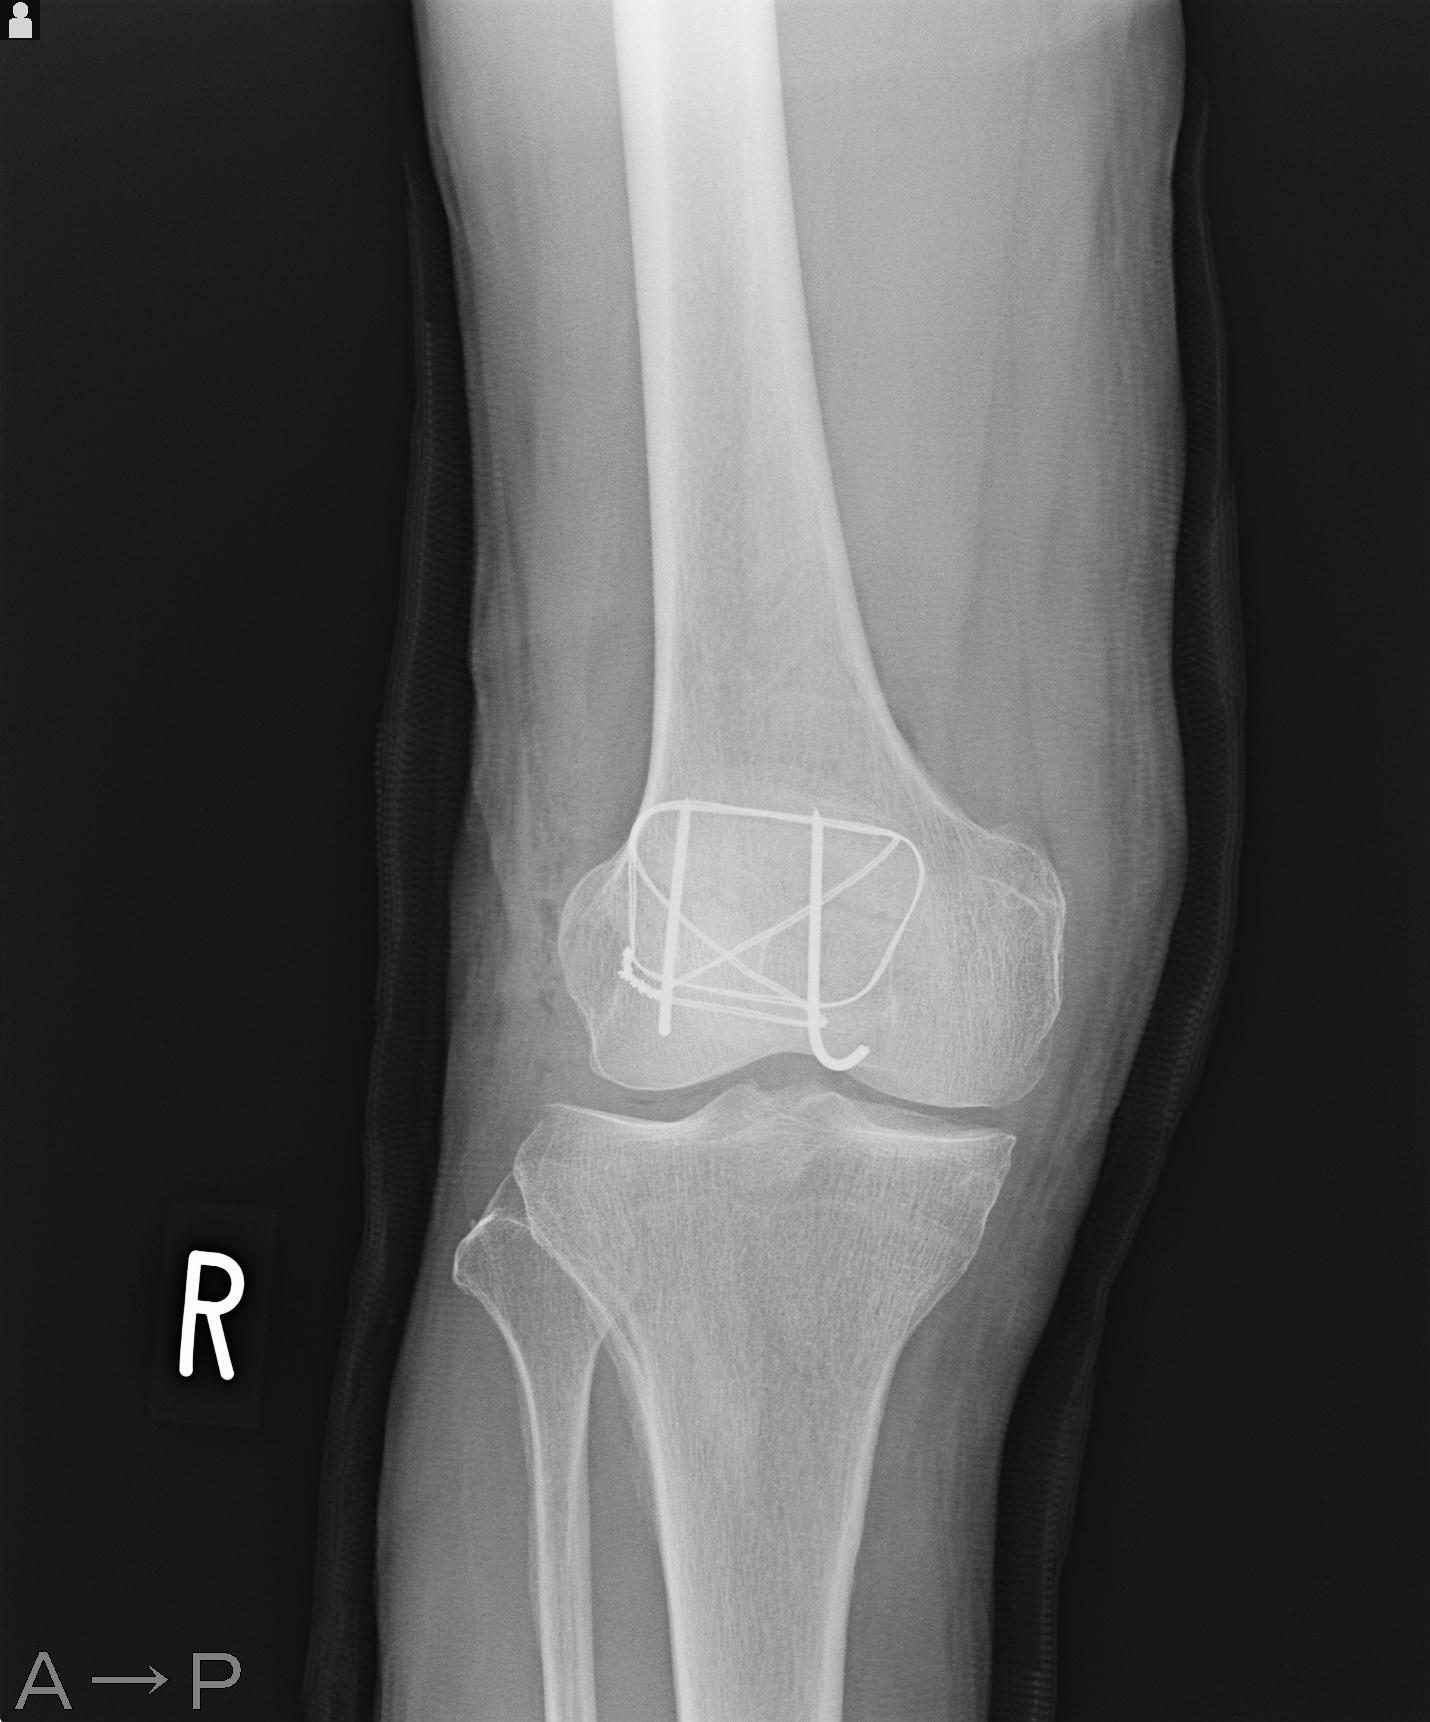

49554 3/13 膝 4R 3/16 4R 1/18 2R 78歳男性 膝蓋骨骨折